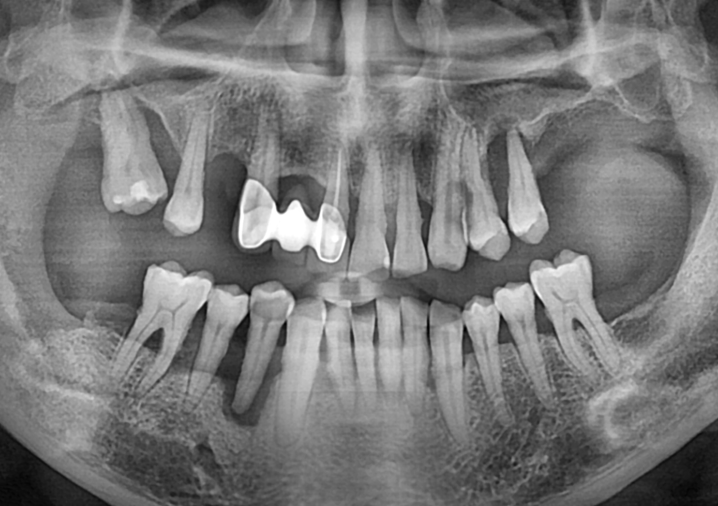

상악동 거상술을 동반한 상하악 임플란트 증례

Before

때로는 처음 오셔서 찍은 x-ray를 봤을 때 탄식이 절로 날 때가 있습니다.

'이거 어떻게 해야 하나..' 싶으면서도 저희를 믿고 따라와 주시는 환자분들을 보면

다시 심기 일전해서 최선을 다해봅니다.

너무 치조골 흡수가 많이 진행되어서 임플란트가 어려울 것 같은 부위에도

다행히 골생성이 잘 되어서 보철까지 마무리가 잘 된 케이스 입니다.